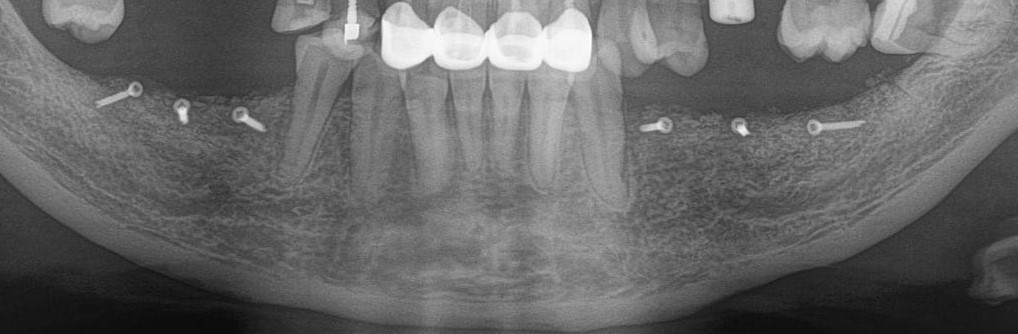

Рентгеновский снимок после имплантации:

И спустя 3.5 месяца на этапе временных коронок (коронок не видно потому, что материал, из которого они изготавливаются, не рентгеноконтрастен):

Пы. Сы.

Пиздюк в лице горизонтального зуба мудрости (на снимке справа) успешно был удалён.